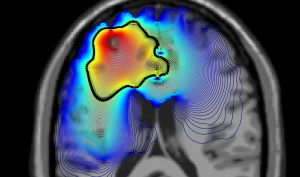

Chemistry image